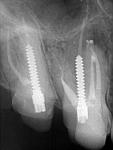

• Ниже (рис. 75-76) представлены фрагменты профильных срезов, наглядно показывающие зоны объединения (устьевая часть, апикальная треть) и расхождения (средняя треть, апекс) корневых каналов 1.5 зуба, а также пример подобной системы из Dental Anatomy & Interactive 3-D Tooth ATLAS (Brown and Herbranson).

| Рис. 75 Обтурация корневых каналов, данные томограммы и 3D диагностики |

Рис. 76 Пространственная иллюстрация эндо-системы (3-D Interactive Tooth ATLAS) |